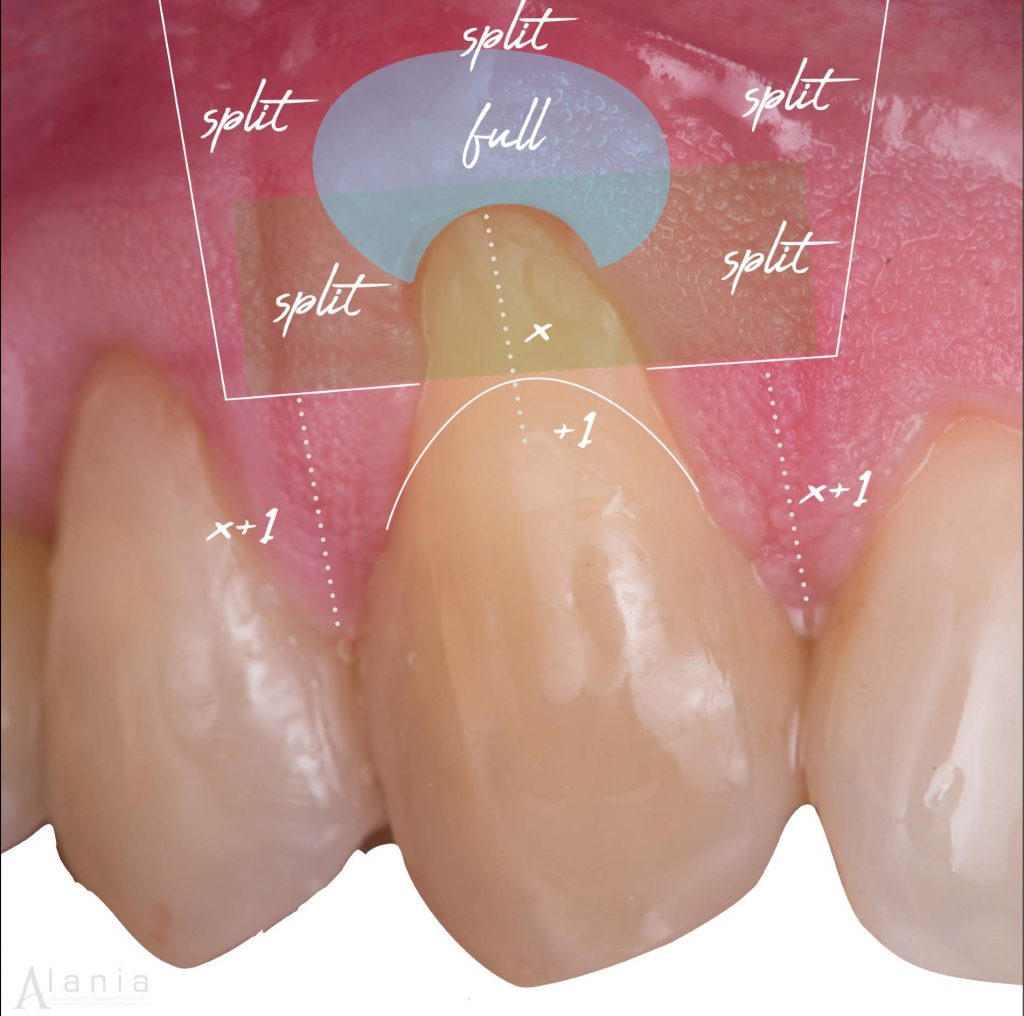

Paso a paso de Colgajo Desplazado Coronal + Injerto de Tejido Conjuntivo

6. Utiliza injerto gingival libre des-epitelializado (IGL - D)

La toma del injerto es uno de los momentos de mayor tensión para un estudiante, debido a las complicaciones que se pueden presentar. Tienes dos técnicas para tomar el injerto: IGL-D e incisión lineal. La incisión líneal permite una cierre por primera intención, resultando en ventajas favorables para la cicatrización y dolor post - operatorio. Sin embargo un IGL- D presenta muchas ventajas:

- Menor tiempo quirúrgico, comparado con tomar el injerto en incisión lineal.

- Menor riesgo vascular, las arterias se encuentran en planos más profundos y con un IGL- D trabajas más cerca a la superficie.

- Mejor calidad de tejido conjuntivo, ya que las fibras están mejor organizadas inmediatamente después del epitelio, a diferencia de planos más profundos donde encontrarás mayor tejido adiposo/ glandular.

- Visión directa, súper importante para tu primera toma de injerto del paladar.